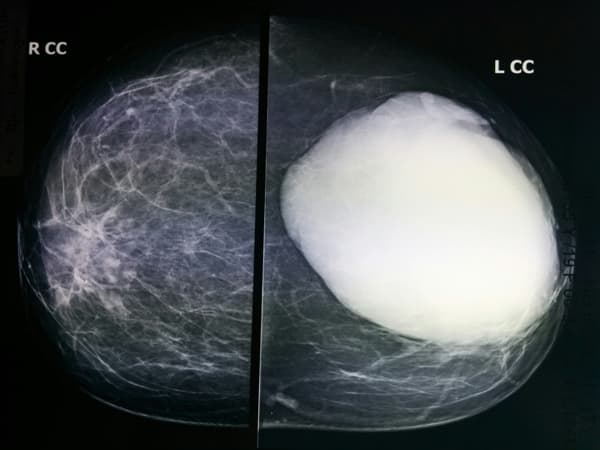

Triệu chứng phổ biến nhất là có một khối u trong vú bạn có thể cảm thấy, sờ thấy khi kiểm tra vú tại nhà hoặc khám lâm sàng với bác sĩ. Khối u diệp thể ở vú có xu hướng phát triển nhanh chóng trong khoảng thời gian vài tuần hoặc vài tháng, với kích thước 2-3 cm hoặc đôi khi lớn hơn.

Sự tăng trưởng nhanh này không có nghĩa là khối u diệp thể là ác tính, bởi các khối u lành tính cũng có thể phát triển nhanh chóng. U diệp thể thường không đau. Nếu không được phát hiện, khối u có thể phình to ra, đẩy vào da. Trong các trường hợp muộn hơn – dù là lành tính, khối u giữa ranh giới hoặc ác tính, khối u diệp thể có thể gây loét hoặc vết thương hở trên da vú.

Giống như các loại u vú hiếm gặp khác, khối u diệp thể có thể khó chẩn đoán vì ít người gặp phải. Khối u diệp thể vú cũng có thể trông giống như bệnh u xơ hóa – một điều kiện lành tính của vú rất thường gặp.